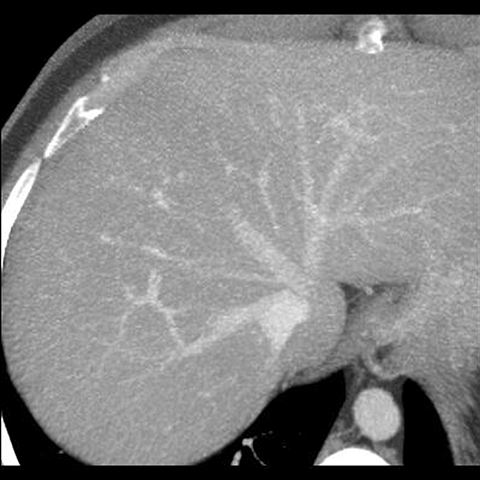

Normal Vessels, CT ( Axial ) [1 of 5]